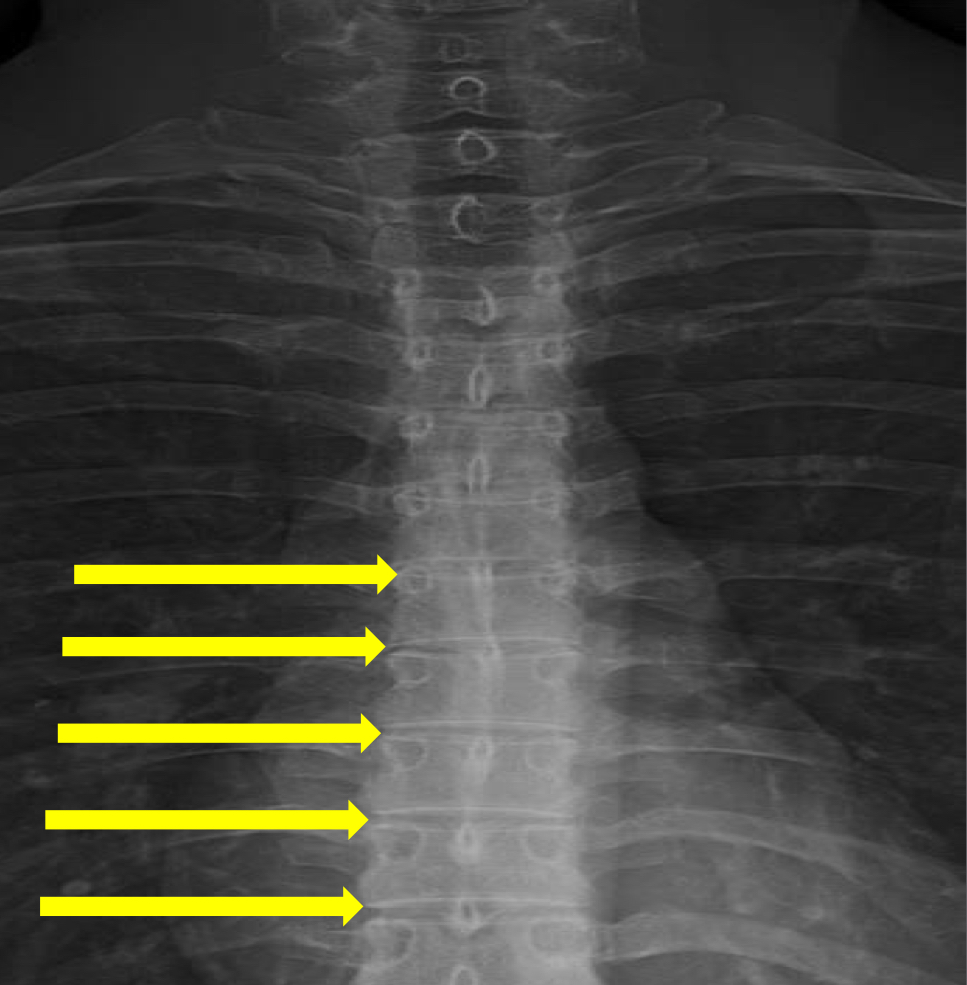

What view is this?

AP (Anterior to Posterior) Thoracic

What is this?

Junction of Laminae

What is this?

Pedicle Shadows

What is this?

Vertebral Waist

What is this?

Inferior Endplate Tips

What is this?

Superior Endplate Tips

What is this?

Disc Spaces